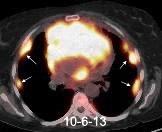

Carcinoma de mama con derrame pleural e implantes metastáticos

Makis W et al. Spectrum of Malignant Pleural and Pericardial Disease on FDG PET/CT. AJR. 2012